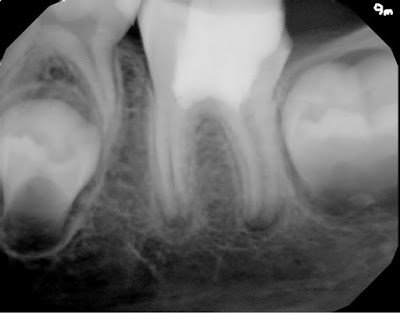

9 month re-eval finds the tooth a symptomatic and functional. Apices continue to develop normally.